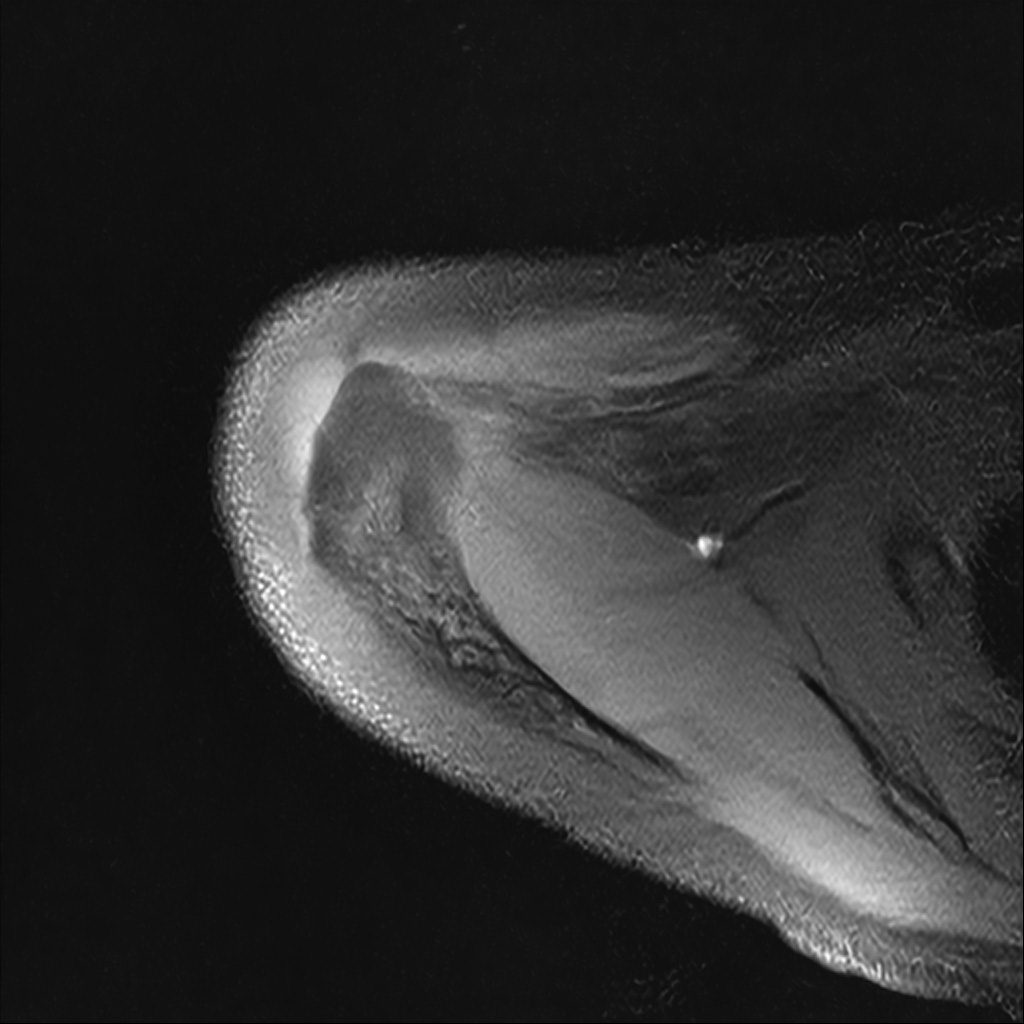

Mri 단면 영상으로 보아 어깨 관절 부위에서 이상 신호가 관찰되고 이는 관절 와순 파열의 가능성을 시사할 수 있습니다.

하지만 이영상만으로 정확한 진단은 불가능하고 정밀한 판단을 위해선 전체 시퀀스와 영상의학과 전문의의 공식판독이 필요합니다 특히 와순 파열은 위치와 동반 병변에 따라 해석이 달라집니다!